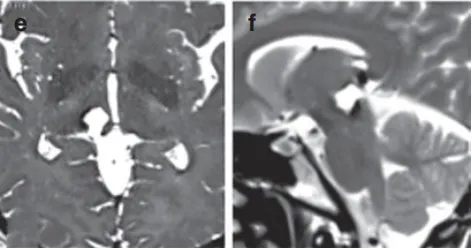

术后MRI影像证实切除效果。

最终,巴教授通过幕下小脑上入路,巧妙避开重要血管结构,为Anne完整切除了血管瘤。术后MRI清晰显示病灶消失,患者未出现新的神经功能缺损,并于术后第10天顺利出院。